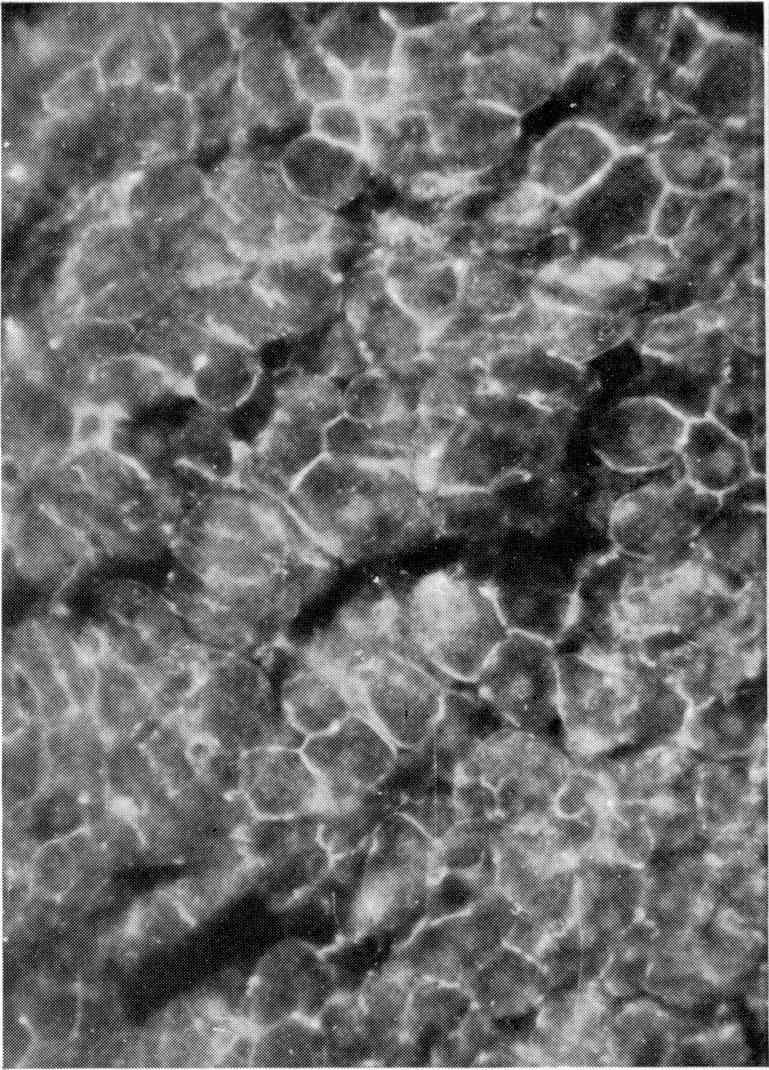

实验性平滑肌抗体。

Experimental smooth muscle antibodies.

Attempts were made to induce smooth muscle antibody (SMA) in rats by various procedures causing cell necrosis. Ligation of a liver lobe and cryosurgical damage to a liver lobe both resulted in subsequent appearance of SMA, provided the damage tissue was not removed. Transfer of the damaged liver tissue to the peritoneal cavity of a normal rat did not result in SMA production in the recipient. The SMA produced showed anti-actin and anti-heavy meromyosin specificity. Damage induced by hepatotoxic agents failed to give rise to SMA.

摘要

人们尝试通过各种导致细胞坏死的方法在大鼠体内诱导产生平滑肌抗体(SMA)。肝叶结扎和肝叶冷冻手术损伤均导致随后出现SMA,前提是损伤组织未被移除。将受损肝组织转移至正常大鼠的腹腔并未导致受体产生SMA。所产生的SMA表现出抗肌动蛋白和抗重酶解肌球蛋白特异性。肝毒性药物诱导的损伤未能产生SMA。